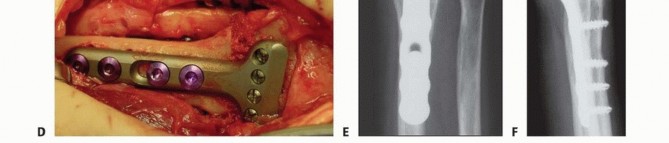

** Intra-articular Distal Radius Osteotomy **Intra-articular osteotomy should be attempted only when there is a simple fracture line that can be clearly identified by direct visualization as well as under image intensification ( TECH FIG 6A-C). Incompletely healed fractures (fewer than 3 to 4 months since injury) are ideal. Depending on the locations of the malunited articular fragments, perform either a dorsal or a volar exposure in the manner detailed earlier. When a dorsal exposure is used, a transverse capsulotomy allows access to the joint and monitoring of the articular osteotomy and realignment. In the case of a volar exposure, the capsule is not incised, but articular exposure may be possible through the osteotomy site. The osteotomy should recreate the original fracture line. This is monitored directly and under image intensification. Reduction is accomplished by soft tissue release and direct fragment manipulation. For many malunions, it is necessary to remove bone or callus from the fracture site to realign the fracture fragment. Callus or bone is removed until the fracture fragment fits properly ( TECH FIG 6D). Provisional Kirschner wires are used to hold the reduction ( TECH FIG 6E,F). The implants are then applied. Dorsally, a single T- or Pi-shaped plate or two 2.0- or 2.4-mm plates (one applied dorsally, ulnar to the tubercle of Lister, and the other applied radially between the first and second dorsal compartments) can be used ( TECH FIG 6G,H). Volarly, a T-shaped plate is usually used. After final plate fixation, provisional fixation is removed. This entire process is monitored using image intensification to confirm appropriate osteotomy site, correction of alignment, and implant placement. Deflate the tourniquet, close the wound, and apply the splint in the manner detailed earlier. 150

### TECH FIG 6 • A-C. PA and lateral radiographs and CT of an intra-articular dorsally angulated malunion. D. A Freer elevator is used under fluoroscopy to reposition the articular fragment. E,F. Intraoperative fluoroscopic views showing provisional correction and fixation. G,H. Final plate and screw fixation. (Copyright Diego Fernandez, MD, PhD.)